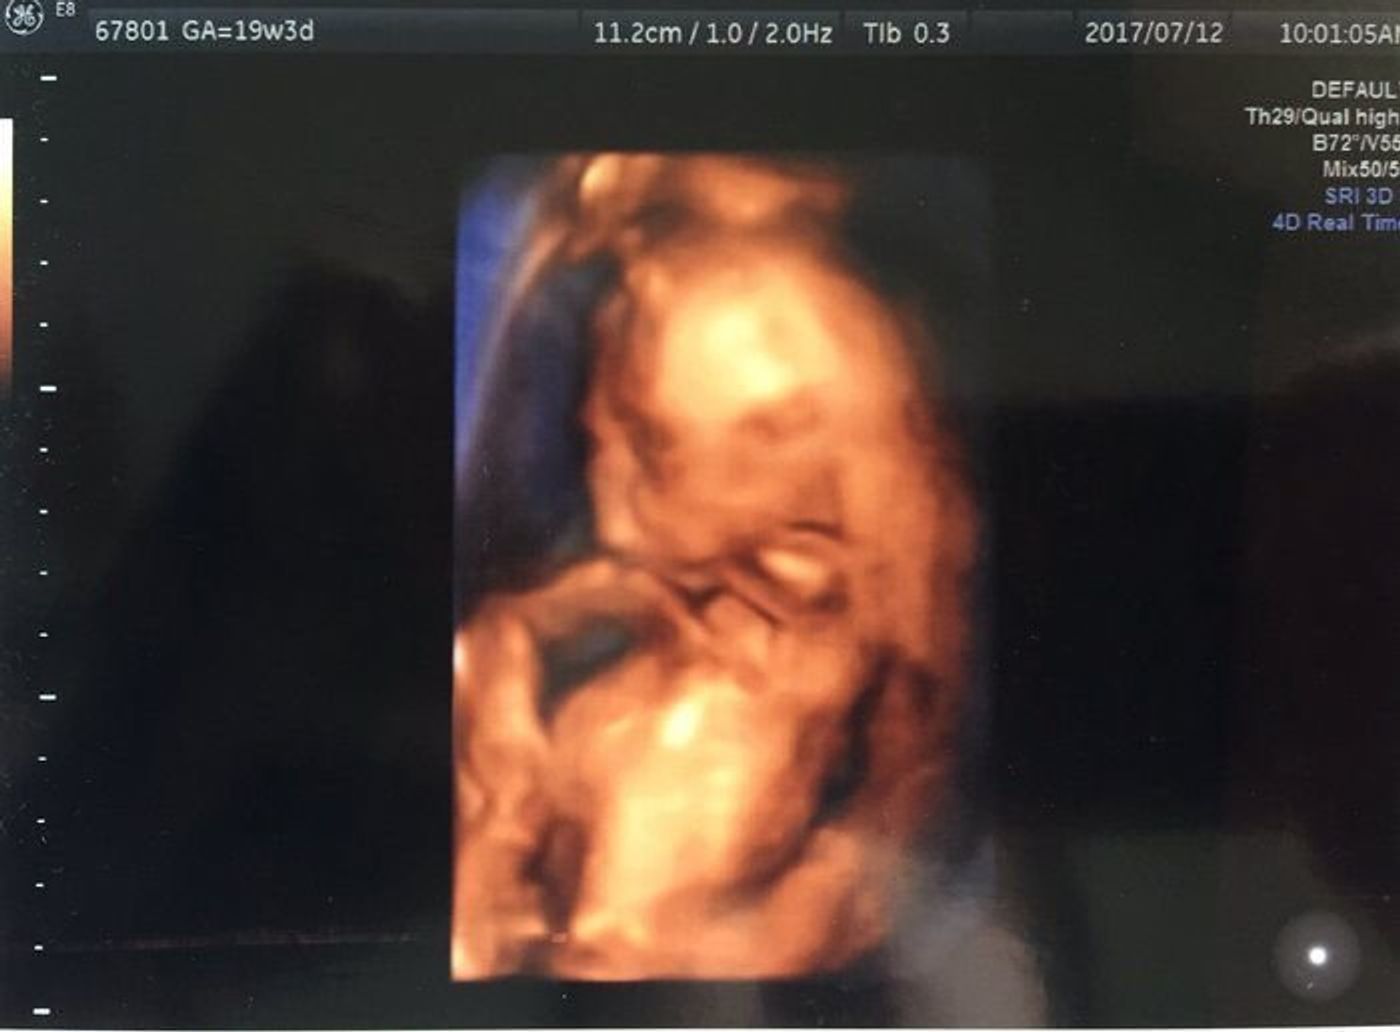

神経が統合されてきたことにより、赤ちゃんの動きも意志をもったものへとなっていきます。 また、からだの動かし方のバリエーションも豊かになっていきます。 五感が発達してくる 神経系が成長することで、脳の前頭葉がはっきりしてくるため 妊娠19週の赤ちゃんの身長は、18㎝程度です。 まるまっている赤ちゃんだと、りんご1個分程度の大きさです。 赤ちゃんはお腹のなかで羊水を飲んだり、おしっこを排出したりを繰り返しています。 性器もほとんど完成し、超音波(エコー)検査でも性別が分かる場合があります。 白っぽかった肌は赤みのある肌色に変わってきたり、3Dエコーで見ると、髪の毛や眉毛も生え始めたの

妊娠19週の胎児体重は正常発育児の954%が 166g~328g 平均体重:247gとなります。 ※1 赤ちゃんの成長速度はどんどん速くなっていき、どんどんしっかりした大きさになっていくので超音波検査などが楽しみになります。 大きく育つということは、その分、腰に負担がかかるということでもあるので、腰痛などには引き続き気をつけなければなりません。 胎児の腎臓や膀胱が完成に 器官形成期 妊娠5ヶ月16~19週の妊婦のおなか 11年9月16日 15年2月6日 妊娠中の妊婦のおなか ママの体は丸みをおびて妊婦らしい体になってきます。 赤ちゃんは羊水の中でよく動き、肺の動きや心臓の鼓動も強くなります。妊娠19週目 妊娠19週目の赤ちゃんの成長 卵がいっぱい: おなかの中の赤ちゃんが女の子であれば、赤ちゃんの生殖器系器官はすでに完成しています。 膣、子宮や卵管が形成され、卵巣には600万個以上の原始卵胞が入っています。 赤ちゃんが産まれる頃、この原始卵胞の数は1万個にまで減少します。 外性器の形成: おなかの中の赤ちゃんが男の子であれば、精巣が形成されて、妊娠10週目頃から

ついに19週に入りました。 旦那さんが帯状湿疹で実家に帰ってもらっているので寂しいけど、時間がたくさんあって楽しいです。 妊娠19週の赤ちゃんは、身長16~cm。 体重0~280g。 赤ちゃんは活発になり、胎動が激しくなります。 性器も完成するので 18週~19週頃の胎動について こんにちは☆ 今正確には18w4dで、明後日で19週に入る初産婦(30歳)です。 初産で体型も太いのですが、胎動は16週頃からと結構早くからポコポコとはっきりと 感じ始め、先週位からはウニ~ウニ~とうねってるような感じもあります。 ここ2、3日かなり激 そして、胎動を感じるようになると、赤ちゃんへの愛情がさらに深まり、毎日何度もお腹に向かって話しかけていました。 妊娠19週のエコーにて。 これはもしや? そして、妊娠19週目(妊娠5ヶ月の終わり)の妊婦健診のこと。 超音波検査を受けていた際にモニター画面を見ていると、あるものが目に飛び込んできました。 おちんちん? 明らかに男児のものであるそれを見て、私